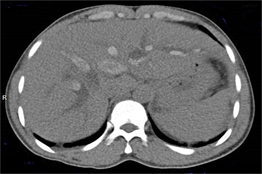

Al segundo día después de la admisión, se complementó estudio con tomografía axial computarizada previa administración de contraste EV (Fig. 3) y se observó: vesícula biliar distendida, colédoco dilatado con litiasis mixta cálcica-biliar, alargada de 13x7mm en su interior y calcificaciones mixtas cálcica-biliares alargadas dentro de los conductos biliares intrahepáticos, los cuales lucían dilatados. En la (fig. 4) se comprobó: páncreas de tamaño normal, con mínima cantidad de líquido y edema peri pancreático, confirmando el diagnóstico de colecistitis litiásica y pancreatitis aguda secundaria, dilatación y litiasis de vías biliares intra y extrahepáticas.

Otras características que pueden detectarse mediante ecografía incluyen cálculos biliares, abscesos hepáticos, "biloma" y colangiocarcinoma. Se puede realizar una aspiración percutánea con aguja fina guiada por ecografía en caso de sospecha de tumor hepático. 11,12 En este caso, la primera investigación por imágenes realizada fue la ecografía de abdomen que muestra un cálculo alargado dentro del colédoco dilatado e imagen ecogénica dentro de las vías biliares intrahepáticas dilatadas y engrosamiento ecogénico adyacente a la pared de la vía biliar. Posteriormente se realizó una tomografía computarizada de abdomen con contraste, para definir la dilatación de la vía biliar que se aprecia mejor en un estudio contrastado, la constitución mixta de las litiasis, propias de los cálculos biliares y sirvió además para descartar otras complicaciones como formación de abscesos, cirrosis hepática, biloma o rotura de la vía biliar con peritonitis y colangiocarcinoma, como vimos la pancreatitis estaba presente como complicación. No se realizó colangiopancreato resonancia a este paciente porque fue remitido a institución terciaria para definir diagnostico y tratamiento, donde fue diagnosticado finalmente con la CPR por los hallazgos de litiasis biliares, estenosis fibrótica y dilatación de las vías biliares.